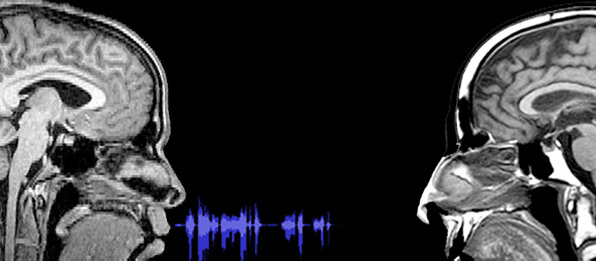

Why the brain makes such snap judgments is

not yet entirely clear, Todorov said. However, he often works with a

sophisticated technological tool for probing brain activity called a

functional magnetic resonance imager (fMRI), and Todorov said some of

his general research suggests that the part of the brain that responds

directly to fear may be involved in judgments of trustworthiness.

"The

fear response involves the amygdala, a part of the brain that existed

in animals for millions of years before the development of the

prefrontal cortex, where rational thoughts come from," he said. "We

imagine trust to be a rather sophisticated response, but our

observations indicate that trust might be a case of a high-level

judgment being made by a low-level brain structure. Perhaps the signal

bypasses the cortex altogether."